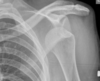

Anterior vs posterior shoulder dislocation on XR

Anterior shoulder dislocation

Posterior shoulder dislocation

Hill Sachs

Bankart lesion